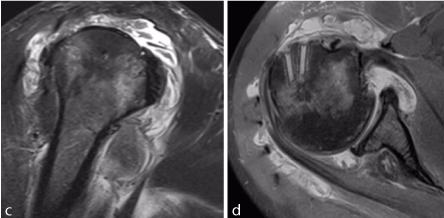

A preoperative MRI was obtained which revealed tendinopathy of the long head of his biceps tendon with fluid tracking down through the tendon sheath and significant synovitis throughout the subacromial space and glenohumeral joint (Figure 1C, D). No abscess or fluid collection was identified.

Figure 1. C, D show oblique coronal and sagittal MRI images of inflammatory changes/diffuse synovitis involving the glenohumeral joint and subacromial space.

While performing the extensive debridement of hyperemic tissues and inspecting the rotator cuff, the previously implanted biofiber had completely disassociated from the repair site and had not integrated into his native tissue. Additionally, the patch appeared to have fragmented into multiple pieces and was encapsulated in inflamed, friable appearing granulation tissue (Figure 2). We took an extended period of time to identify these fragments of the patch and removed them all in their entirety. We identified the biceps tendon sheath which was indeed quite inflamed and hyperemic with hypertrophic appearance. The tendon sheath was opened with additional fragments of the biofiber identified therein.

Figure 2. A-C Arthroscopic views show significant inflammatory response and retained sutures from posterior (A, B) and lateral (C) portals. D shows the inflammatory response encasing a remnant of the patch during arthroscopic removal from the lateral portal.